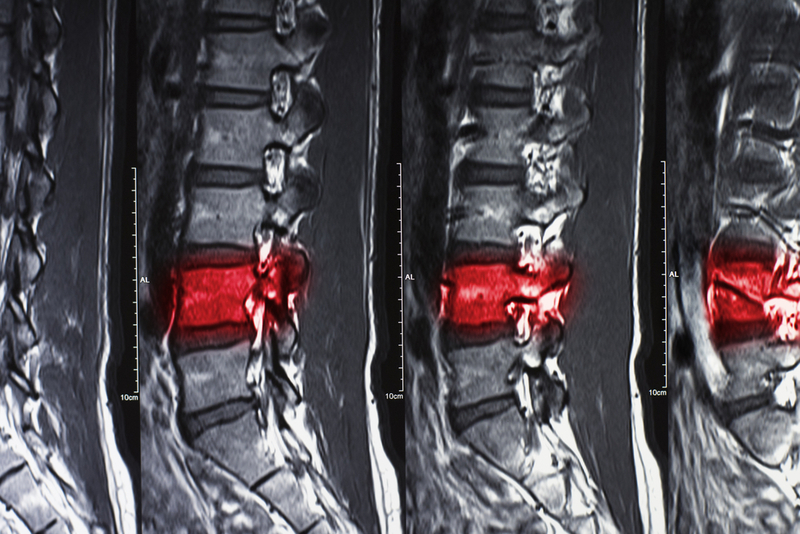

Protein vital for wound healing after spinal cord injury, study explains

A recent research has shed light on the fact that an axon guidance protein--Plexin-B2--in the central nervous system plays a vital role in wound healing and neural repairing spinal cord injury.

The study's findings, published in Nature Neuroscience, could aid the development of therapies that target axon guidance pathways for more effective treatment of SCI patients. Conducted at the Icahn School of Medicine at Mount Sinai, the study found that the deletion of Plexin-B2 in microglia and macrophages impaired corralling, which led to tissue damage, inflammatory spillover, and hindered the regeneration of axons (slender part of a nerve cell where impulses are conducted).

Tissue repair after SCI requires the mobilization of immune and glial cells to form a protective barrier that seals the wound, facilitates debris clearing and contains inflammation. To build this barrier, a process called corralling involves wherein microglia (immune cells in the CNS) and macrophages (immune cells that originate from blood) form a barrier around the lesion that separates healthy and necrotic tissue. During the study, researchers found that this corralling begins early in the healing process and requires Plexin-B2, a protein that facilitates the movement of immune cells by steering them away from colliding cells.